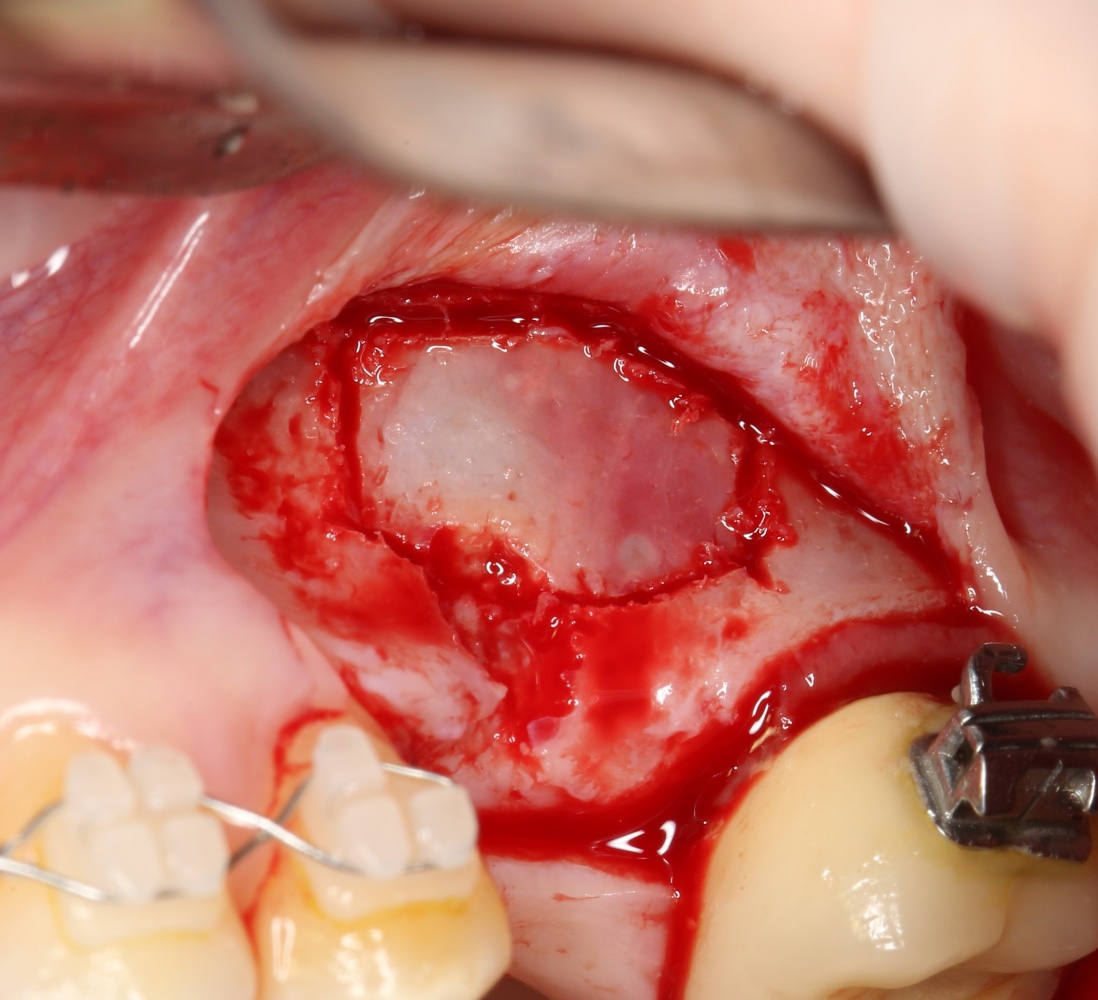

Синуслифтинг: что делать при перфорации слизистой оболочки гайморовой пазухи?